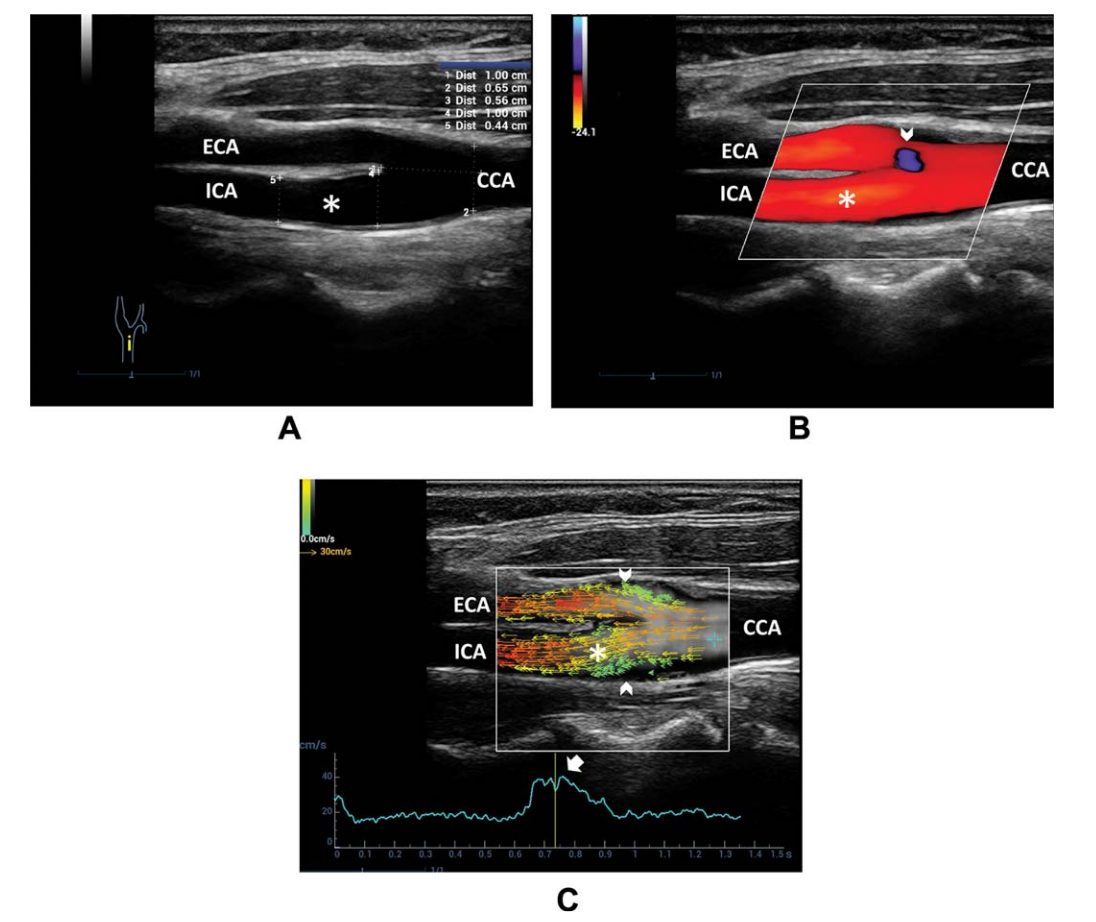

Figure 2. Pulsed-Wave Doppler Acquisition

Figure 9. A, B-mode US of the carotid bifurcation indicates a reduction in diameter from the CCA to ICA. B, Color Doppler imaging shows a uniformly colored flow pattern throughout the ICA (asterisk). A small area of an ambiguous signal is seen at the external carotid artery (ECA) entrance (arrowhead). C, Vector flow imaging frame at the systolic peak shows blood flowing upstream through the entire diameter in the ICA sinus.The main flow is depicted by parallel red/orange vectors; a flow separation area, without recirculation, is highlighted by slow green vectors upstreaming near the boundary of the carotid bifurcation.